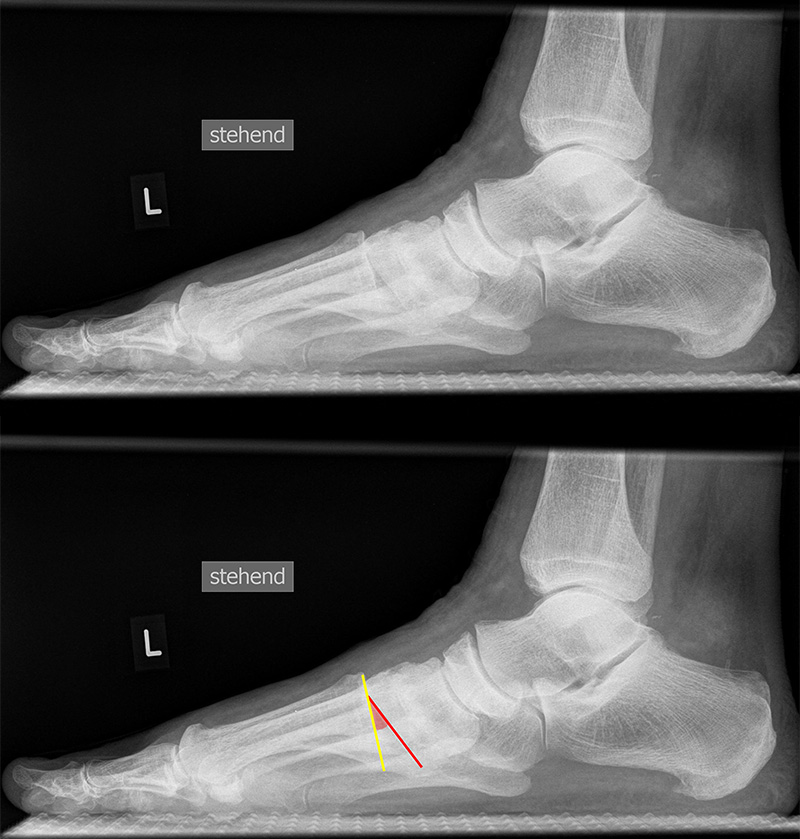

Vermessung der belasteten Aufnahmen des Fußes

Winkelmessungen am Fußskelett beziehen sich sämtlich auf belastete Aufnahmen 6. Die folgenden Aufnahmen zeigen die üblicherweise verwendeten Winkelmaße und ihre Definition. Viele Fehlstellungen des Fußes betreffen den Vor- und Rückfuß. Dies sollte bei der Beurteilung der Bilder und der Therapieplanung stets berücksichtigt werden.

TMT-1-Gelenk lateral (Tarsometatarsale-1-Gelenk)

In der Seitaufnahme wird eine plantare Öffnung des TMT-1-Gelenks als Indikator für eine Instabilität gewertet. Coughlin et al. 5 definierten einen Winkel zwischen der proximalen Gelenkfläche des Os metatarsale I (gelb) und der distalen Gelenkfläche des Os cuneiforme I (rot). (Norm: ±0° 5).

Beurteilung von Fehlstellungen des Mittel- und Rückfußes

Zur Vollansicht und zum Lesen der Bildbeschreibung bitte die Bilder anklicken.

Achsen auf der lateralen Aufnahme

Die Grundlinie (blau) ist definiert durch den tiefsten Punkt der Sesambeine und den tiefsten Punkt des Kalkaneus.

CPA (Calcaneal pitch angle): Der Kalkaneus Inklinationswinkel liegt zwischen der Grundlinie (blau) und der plantaren Begrenzung des Kalkaneus (grün) (Norm 20,8 ± 4,1° 11, 15-39° (Zwipp 2014)).

LTCA (Lateral talocalcaneal angle): Der laterale talokalkaneare Winkel liegt wird gebildet aus der Talusachse (türkis) und einer Verbindungslinie zwischen dem Oberrand des Proc. ant. Calcanei und der dorsalen Begrenzung des Kalkaneus (gelb). (Norm: 33° Range 25-45°) 1213).

LTMA (Lateral talometatarsal angle, Syn. Meary’s angle): Der laterale talometatarsale Winkel wird gebildet aus der Achse des Os metatarsale I (rot) und der Achse des Talus (türkis). (Norm: 7,1 ± 10,8 11).

Böhler-Winkel (Syn. Tubergelenkwinkel)

Es wird eine Linie vom Proc. ant. calcanei zur dorsalen Facette des Subtalargelenks gezogen (rot). Die zweite Linie verläuft von der kranialen Begrenzung des Tuber calcanei zum Subtalargelenk (gelb). Gemessen wird der nach dorsal offene Winkel zwischen den beiden Linien (Norm: 22-48° 9).

Meary’s angle dorsoplantar (Talo-Metatarsale-I-Winkel)

Der Talo-Metatarsale-I-Winkel wird auf den belasteten dorsoplantaren und lateralen Aufnahmen bestimmt. Es wird jeweils die Achse durch den Talushals gelegt (grün) und der Winkel zur Achse des Os metatarsale I bestimmt (rot). Der Winkel liefert keine Information darüber, an welcher Stelle sich die Fehlstellung befindet. Auch kann ein Serpentinen-Fuß „physiologische“ Werte liefern, da Os metatarsale I und Talushals parallele Achsen aufweisen, obwohl eine erhebliche Fehlstellung vorliegt 11. (Norm: 7,7 ± 8,2° 11).

Meary’s angle lateral (Talo-Metatarsale-I-Winkel)

Der Talo-Metatarsale-I-Winkel wird auf den belasteten dorsoplantaren und lateralen Aufnahmen bestimmt. Es wird jeweils die Achse durch den Talushals gelegt (grün) und der Winkel zur Achse des Os metatarsale I bestimmt (rot). Der Winkel liefert keine Information darüber, an welcher Stelle sich die Fehlstellung befindet. Die Fehlstellung kann das Talonaviculare-Gelenk (TN-Gelenks), das Naviculocuneiforme-Gelenk (NC-Gelenks) oder des Tarsometatarsale-I-Gelenk (TMT-I-Gelenks) betreffen, bzw. auch mehrere Gelenke einbeziehen. Der Talo-Metatarsale-I-Winkel gilt als zuverlässigster Parameter in der Differenzierung symptomatischer Pes planovalgus-Deformitäten gegenüber einer Kontrollgruppe 11.  (Norm: 7,1 ± 10,8 11).